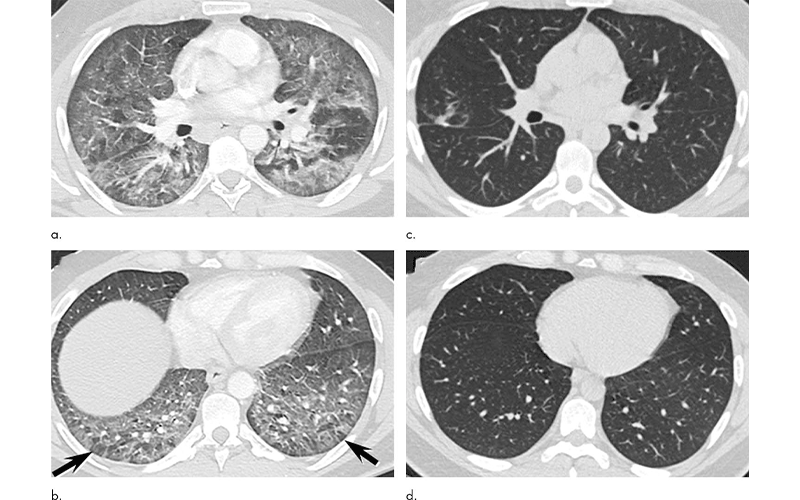

Gotway Fig. 5 feature

Images in a 39-year-old man with respiratory failure hospitalized for 10 days with an electronic cigarette or vaping product use–associated lung injury manifesting as an acute lung injury pattern at CT with some CT features suggesting a hypersensitivity pattern. (a, b) Axial enhanced CT images through the (a) mid and (b) lower lungs at presentation show multifocal areas of ground-glass opacity with prominent lobular low attenuation in the bases (arrows) suggesting small airway obstruction in addition to the ground-glass opacity. (c, d) Axial unenhanced CT images through the (c) mid and (d) lower lungs obtained 64 days after presentation show complete clearing of lung parenchymal abnormalities. Right middle lobe opacity (c) reflects site of surgical lung biopsy, which showed acute lung injury with organization, but no granulomas or other features typical of hypersensitivity pneumonitis.